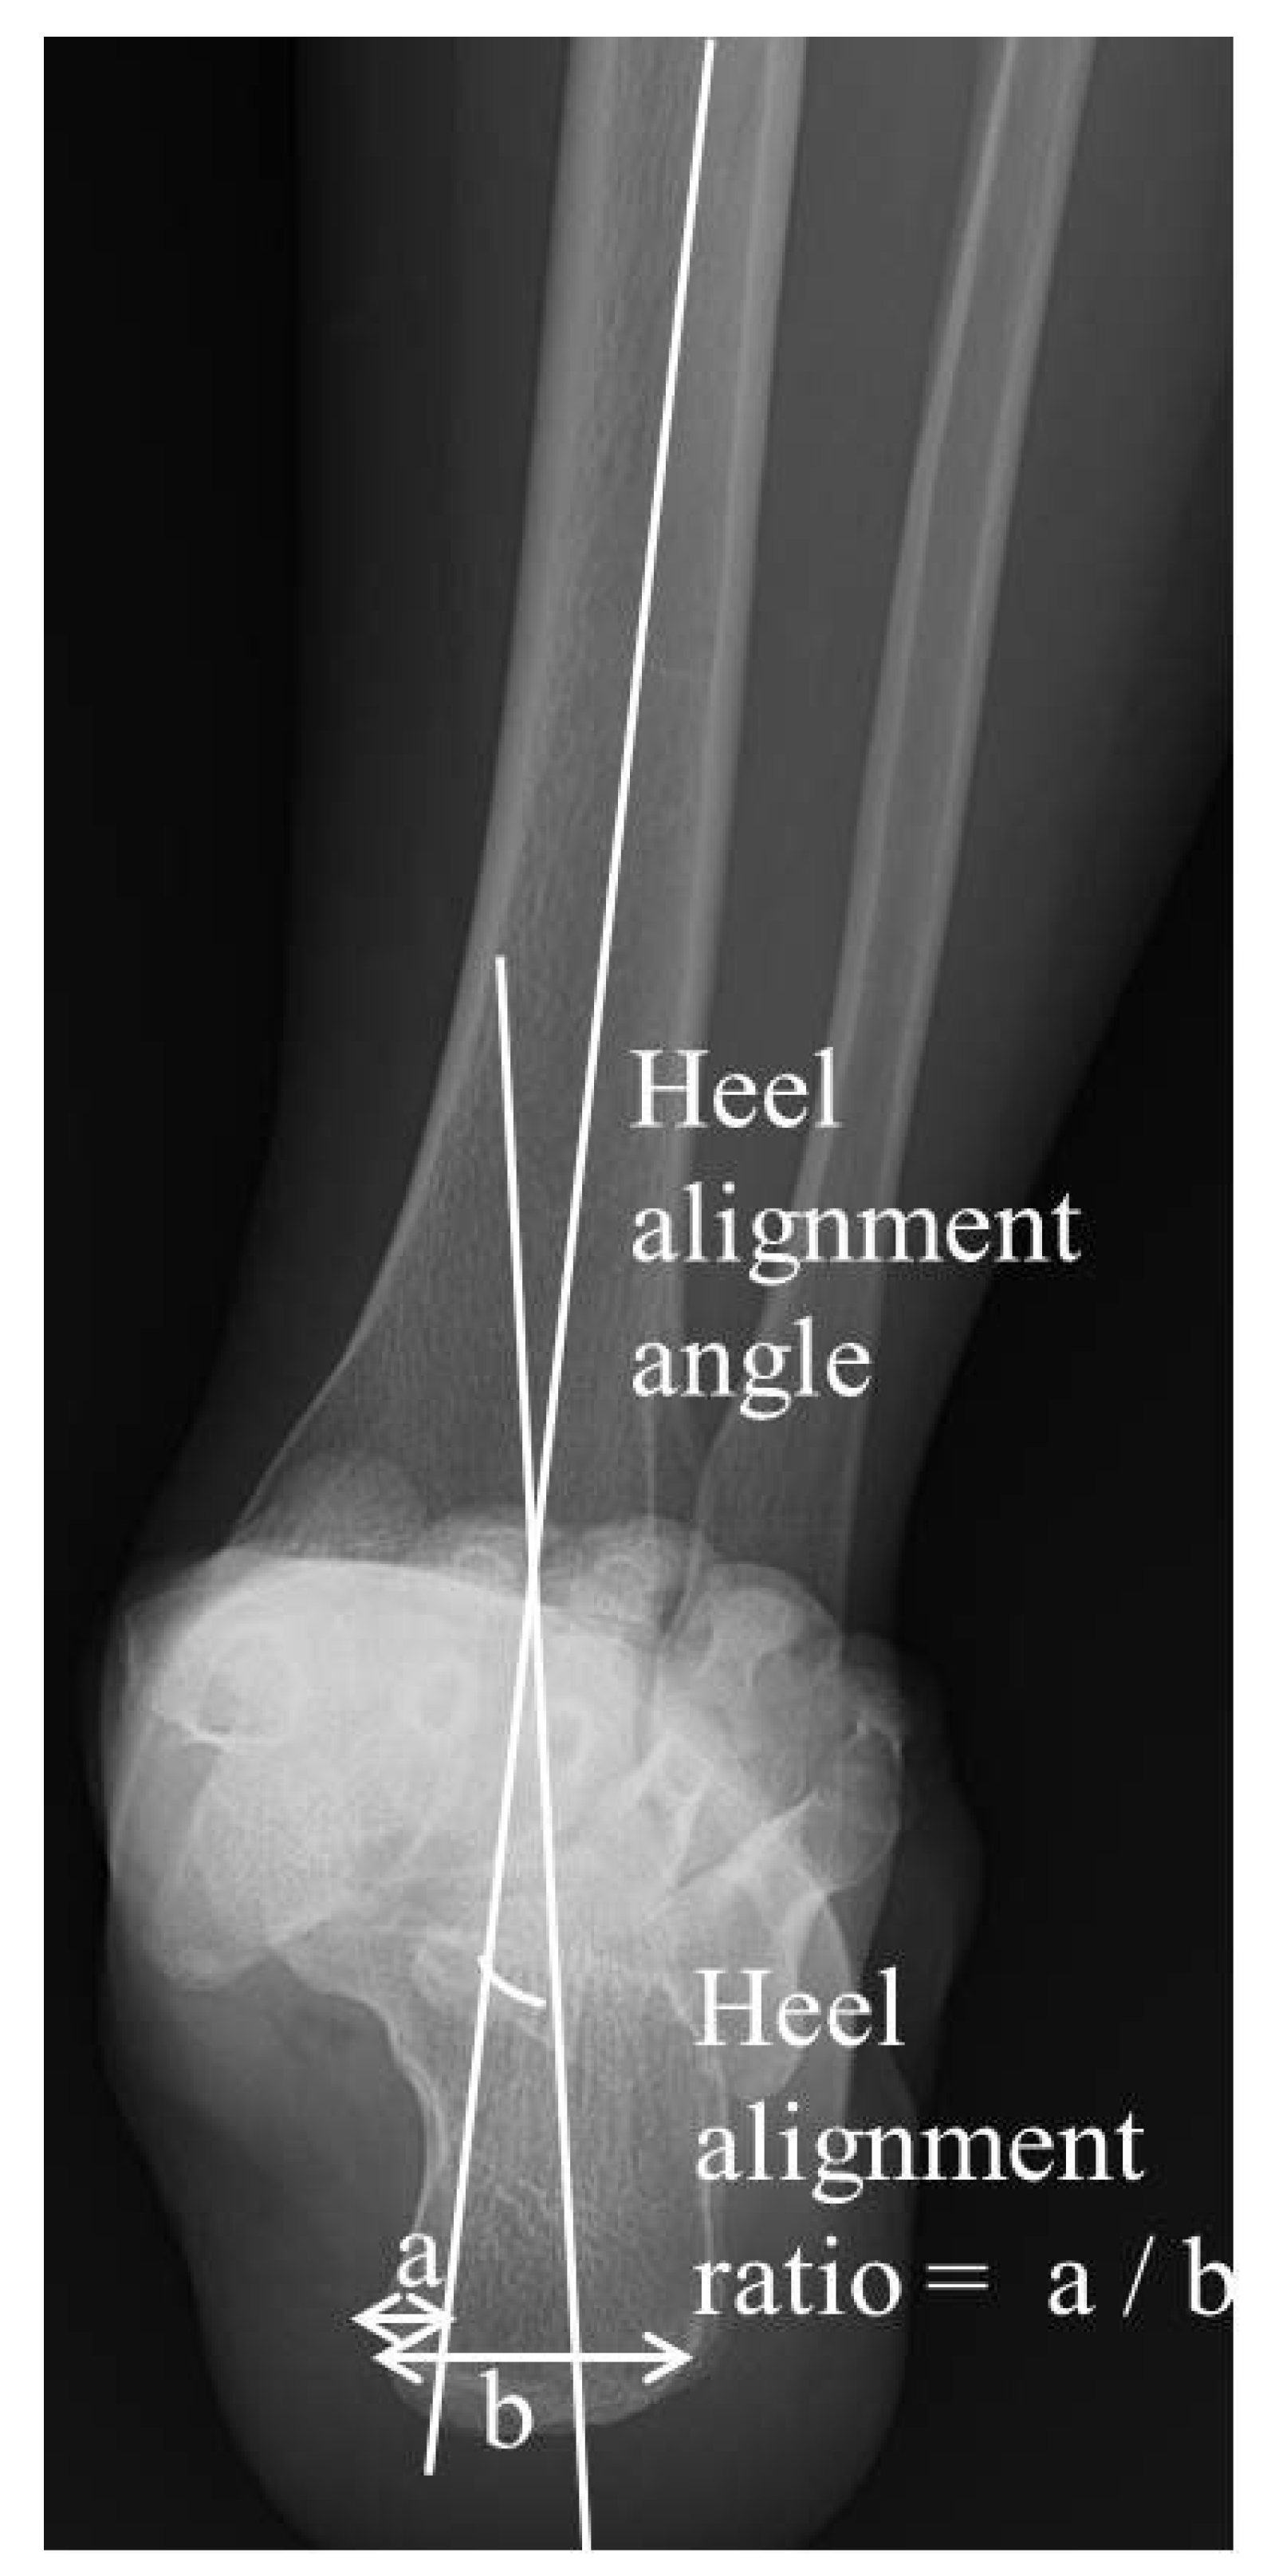

Radiographic measurements were derived from the obtained hindfoot alignment view, NWBCT and WBCT scans, focusing on hindfoot and subtalar joint parameters using defined anatomical landmarks and angles. The hindfoot alignment view is a radiographic projection (20 degrees) obtained to measure the hindfoot angle during weightbearing, typically an anteroposterior (AP) view of the foot that allows the assessment of alignment between the tibia and calcaneus. To assess the hindfoot alignment in a simple radiograph, two measurements were obtained for the hindfoot alignment view: (1) the hindfoot alignment angle (HAA) and (2) the hindfoot alignment ratio (HAR) [20,21]. The hindfoot alignment angle (HAA), which is an angle between the tibial axis and calcaneal axis, was measured and expressed as a positive number when it was in valgus. The hindfoot alignment ratio (HAR) was obtained by dividing the width of the calcaneus medial to the tibial axis by calcaneal width at its widest portion on the alignment view (Figure 2). The tibial axis was defined using a line perpendicular to the distal tibial joint surface, while the calcaneal axis was determined by drawing a line along the medial contour of the calcaneus on the most posterior image that includes both the tibia and calcaneus.

Thus, we determined the talocalcaneal distance (TCD) at the Gissane angle as the radiographic parameter of subtalar joint during upright weightbearing, which could be be predicted by measuring the hindfoot valgus alignment in simple radiograph. Referencing prior cadaver study [27], we postulated that the talocalcaneal osseous contact was less than 2 mm of talocalcaneal distance at the Gissane angle in WBCT. In the ROC curve analysis, hindfoot alignment angle (HAA) had the greater AUC (area under the curve = 0.807, 95% CI = 0.703–0.911) compared with the hindfoot alignment ratio (HAR) (area under the curve = 0.323, 95% CI = 0.197–0.449), suggesting that HAA is the best radiographic parameter for predicting the contact condition between talus and calcaneus at the Gissane angle (sinus tarsi bony impingement) [28]. The ROC curve analysis identified a threshold HAA value of 9.25°, achieving 73.0% sensitivity and 81.8% specificity for predicting talocalcaneal contact, with an AUC of 0.807 (Figure 6).

There are three established methods for measuring hindfoot alignment: HAA, hindfoot alignment ratio (HAR) and hindfoot moment arm (HMA) [21]. In this study, we measured hindfoot alignment separate from angle and ratio on the hindfoot alignment view. In this study, we measured hindfoot alignment separate from angle and ratio in the hindfoot alignment view. Hindfoot alignment is assessed by both angle and ratio in the hindfoot alignment view, which allows for the evaluation of both angulation and translation due to variations in hindfoot deformities. For instance, hindfeet with minimal valgus angulation but large translation may exhibit significant subtalar joint changes. Thus, subtalar joint changes during upright full weightbearing were evaluated according to two hindfoot alignment view parameters (HAA and HAR). HAA is straightforward to measure and demonstrates high intra- and inter-observer reliability, making it a preferred parameter for routine clinical practice, and while HAR provides additional insights into hindfoot proportional relationships, its complexity limits clinical application. HMA was not included in this study due to the insufficient validation of its utility and reliability [21,37].

This study evaluated the utility of two hindfoot alignment view measurements for identifying talocalcaneal osseous contact in patients with hindfoot valgus malalignment. A prior cadaver study reported a mean cartilage thickness of 0.98 ± 0.16 mm in the talar-subtalar joint [27]. Based on this value, talocalcaneal osseous contact related to sinus tarsi bony impingement was defined as a talocalcaneal distance of less than 2 mm at the Gissane angle in WBCT. The HAA demonstrated the highest accuracy for predicting talocalcaneal osseous contact, with a 73% sensitivity and an 81.8% specificity using a cutoff value of >9.25°. This underscores HAA’s clinical utility in resource-limited settings without WBCT access. However, the ROC analysis also highlights that identifying talocalcaneal osseous contact through radiographic measurements may not detect symptomatic talocalcaneal osseous impingement directly. Nevertheless, the early detection of suspected cases through this method is valuable, as it may prevent the progression of adjacent sclerosis or cystic changes. Although HAR showed weaker predictive power compared to HAA [28], it remains a statistically relevant parameter for assessing hindfoot valgus alignment. Combining these measurements enhances diagnostic accuracy, facilitating the early detection of subtalar joint pathologies and preventing severe deformities.